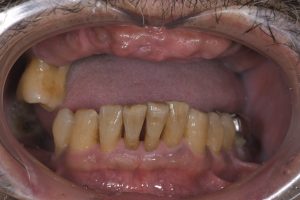

ちなみに治療前の状態です。

下の奥歯2本もインプラントの歯です。

こちらの1番奥の歯は、ジルコニアセラミック冠です。